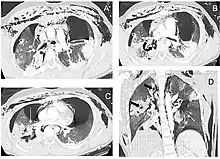

A patient with traumatic complete disruption of the right bronchus. Computed tomography scan following emergency chest tube drainage. Axial 1.25 mm thick sections with a lung window. (a) Persistent bilateral pneumothorax, pneumomediastinum and extensive subcutaneous emphysema. (b) Multiple lucencies around the right bronchial tree (curved arrow) precluding the correct recognition of the bronchial rupture. (c) The Macklin effect around the right lower pulmonary vein (white arrow). (d) Coronal view demonstrating multiple areas of alveolar consolidation in the right upper and lower lobes: intraparenchymal lucencies resulting from lung lacerations are visible on the right side (thick arrows).

Rapid diagnosis and treatment are important in the care of TBI;[6] if the injury is not diagnosed shortly after the injury, the risk of complications is higher.[11] Bronchoscopy is the most effective method to diagnose, locate, and determine the severity of TBI,[6][10] and it is usually the only method that allows a definitive diagnosis.[23] Diagnosis with a flexible bronchoscope, which allows the injury to be visualized directly, is the fastest and most reliable technique.[8] In people with TBI, bronchoscopy may reveal that the airway is torn, or that the airways are blocked by blood, or that a bronchus has collapsed, obscuring more distal (lower) bronchi from view.[3]

Chest x-ray is the initial imaging technique used to diagnose TBI.[17] The film may not have any signs in an otherwise asymptomatic patient.[15] Indications of TBI seen on radiographs include deformity in the trachea or a defect in the tracheal wall.[17] Radiography may also show cervical emphysema, air in the tissues of the neck.[2] X-rays may also show accompanying injuries and signs such as fractures and subcutaneous emphysema.[2] If subcutaneous emphysema occurs and the hyoid bone appears in an X-ray to be sitting unusually high in the throat, it may be an indication that the trachea has been severed.[4] TBI is also suspected if an endotracheal tube appears in an X-ray to be out of place, or if its cuff appears to be more full than normal or to protrude through a tear in the airway.[17] If a bronchus is torn all the way around, the lung may collapse outward toward the chest wall (rather than inward, as it usually does in pneumothorax) because it loses the attachment to the bronchus which normally holds it toward the center.[6] In a person lying face-up, the lung collapses toward the diaphragm and the back.[23] This sign, described in 1969, is called fallen lung sign and is pathognomonic of TBI (that is, it is diagnostic for TBI because it does not occur in other conditions); however it occurs only rarely.[6] In as many as one in five cases, people with blunt trauma and TBI have no signs of the injury on chest X-ray.[23] CT scanning detects over 90% of TBI resulting from blunt trauma,[3] but neither X-ray nor CT are a replacement for bronchoscopy.[6]